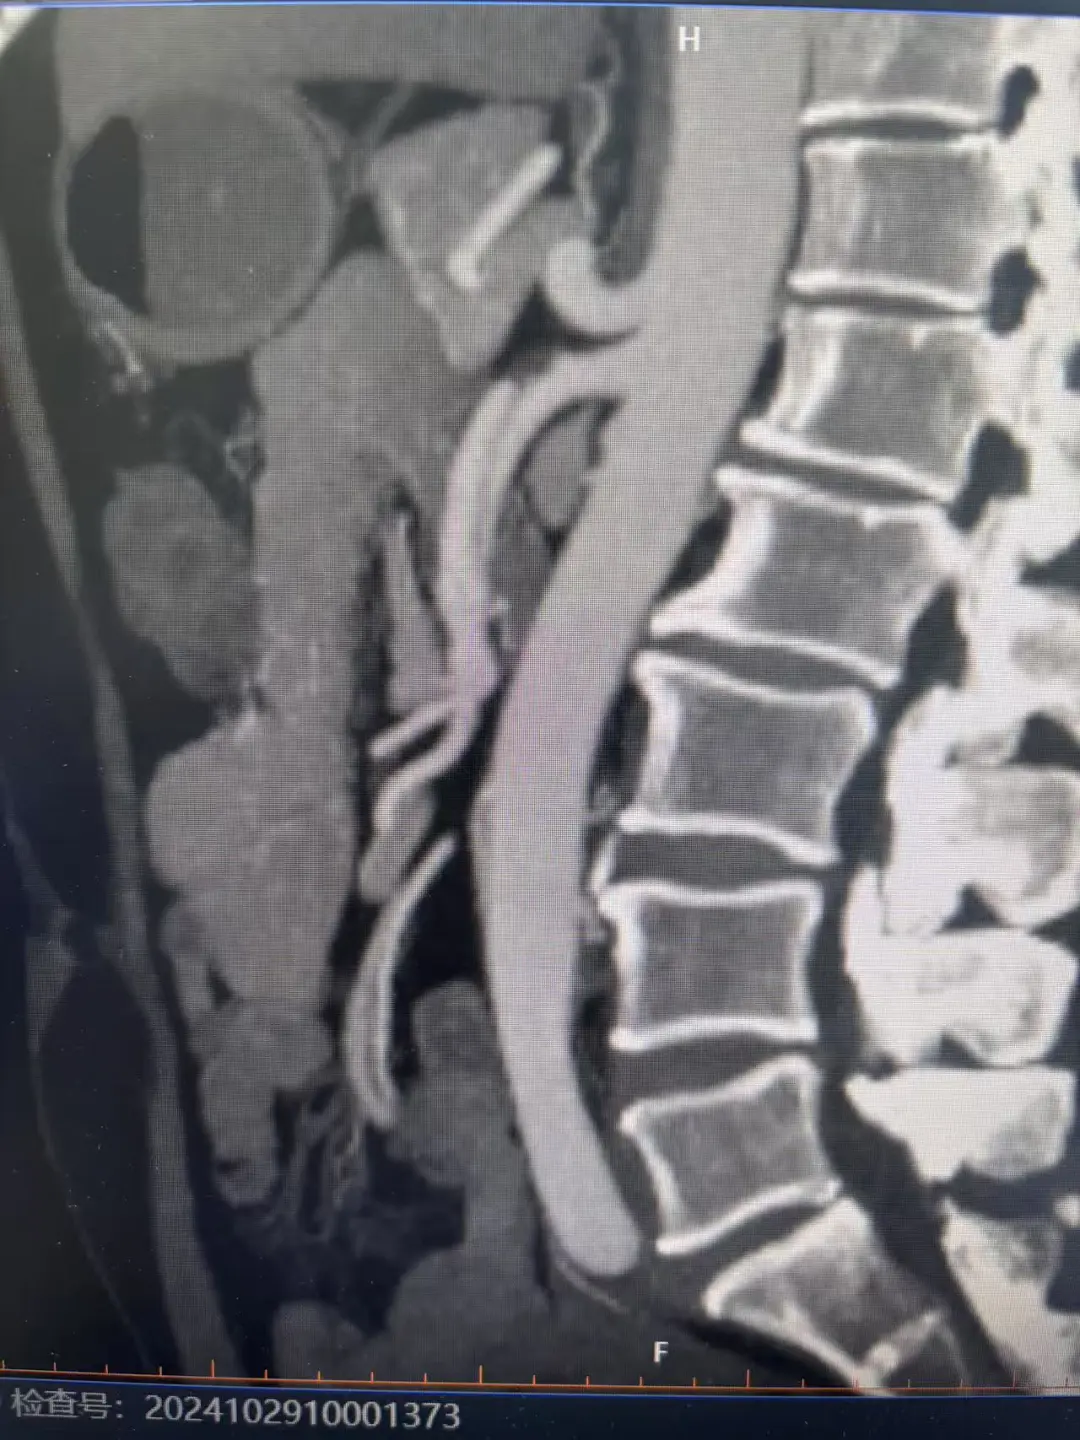

医生接诊后,仔细询问情况并进行了体格检查以及进一步的影像检查。全腹部增强CT提示:肠系膜上动脉改变,考虑壁间血肿或局限性夹层伴假腔血栓化,局部管腔中重度狭窄。

为彻底拆除这个“*”,蕲春县人民医院介入血管科朱林主任复阅陈先生检查的影像资料后,评估患者病情,陈先生是肠系膜上动脉夹层合并血栓形成,存在肠管缺血风险,若错过最佳治疗时机,血管一旦完全闭塞,将导致肠管缺血坏死,后果不堪设想。应立即行介入肠系膜上动脉支架置入术重建血运。

完善术前准备后,先进行肠系膜上动脉造影检查,进一步明确肠系膜上动脉夹层合并血栓形成的诊断,夹层撕裂较长,且肠系膜上动脉主干真腔及远端分支部分真腔明显受压变窄,影响肠管供血,肠管缺血坏死风险高,且陈先生持续腹痛不能缓解,有肠系膜上动脉支架成形术指征。

(左图术前造影,右图支架置入后)

朱林主任带领介入血管科手术团队,克服患者肠系膜上动脉长段夹层、真腔明显狭窄、动脉角度刁钻等困难,将导丝顺利通过右侧股动脉入路,置于肠系膜上动脉远端正常分支,路图引导下缓慢精准释放裸支架一枚,即刻造影显示肠系膜上动脉狭窄消失,远端肠管供血明显改善。